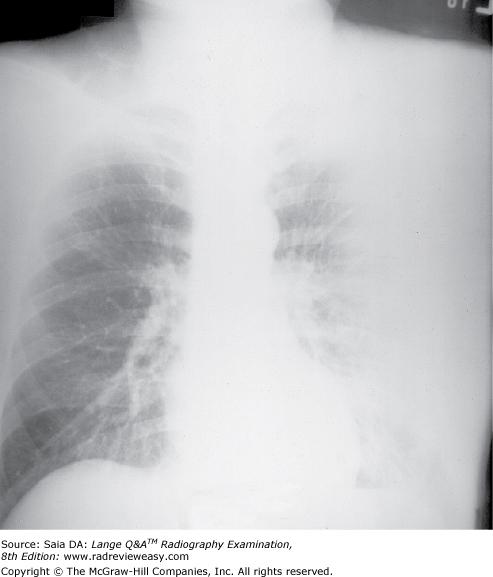

The radiograph seen below illustrates incorrect use of

A collimator

B grid

C AEC

D focal spot

-An upside-down focused grid presents its lead strips in the opposite direction to that of the x-ray beam. This results in severe grid cutoff everywhere except in the central portion of the radiographic image. Severe grid cutoff of chest anatomy can be seen outside the central exposed area. A misaligned collimator would not show such symmetrical loss of receptor exposure, nor would an incorrectly selected AEC photocell. Focal spot is unrelated to receptor exposure.